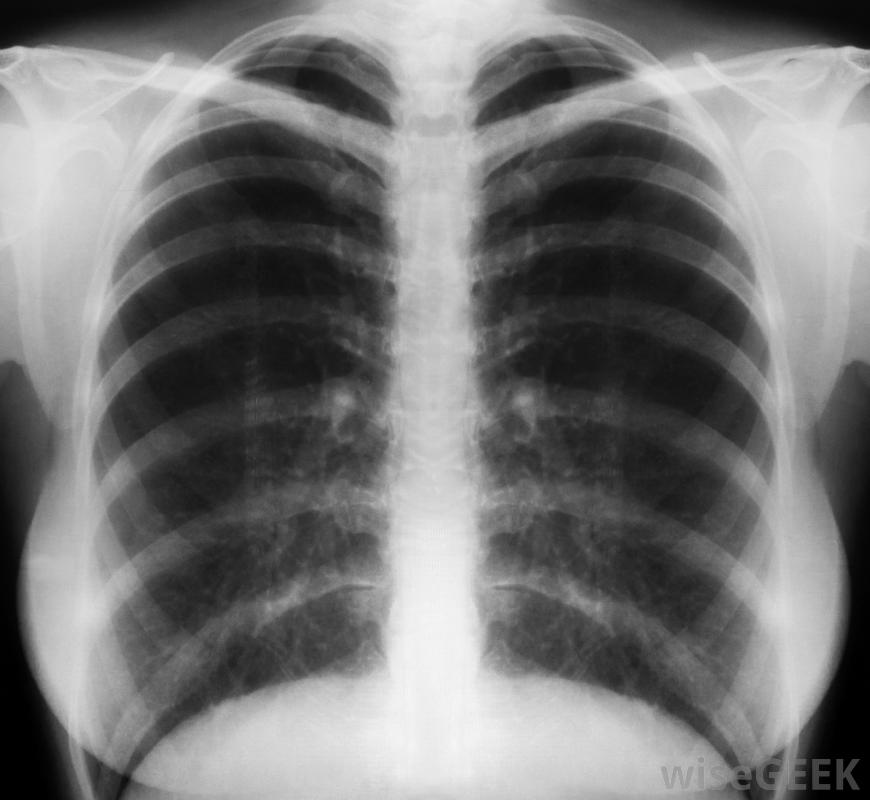

如果懷疑肺部感染或其他損傷,可要求進行胸部x光檢查。

如果懷疑有其他疾病,例如肺部感染,或者如果最近有明顯的損傷,醫生可能會提供進一步的檢查,這可能包括胸部x光檢查。當疼痛歸因于這些情況之一時,肋軟骨炎的治療也將包括治療根本原因。在某些情況下,醫生會建議對胸部進行熱敷或冷敷,以減輕疼痛。